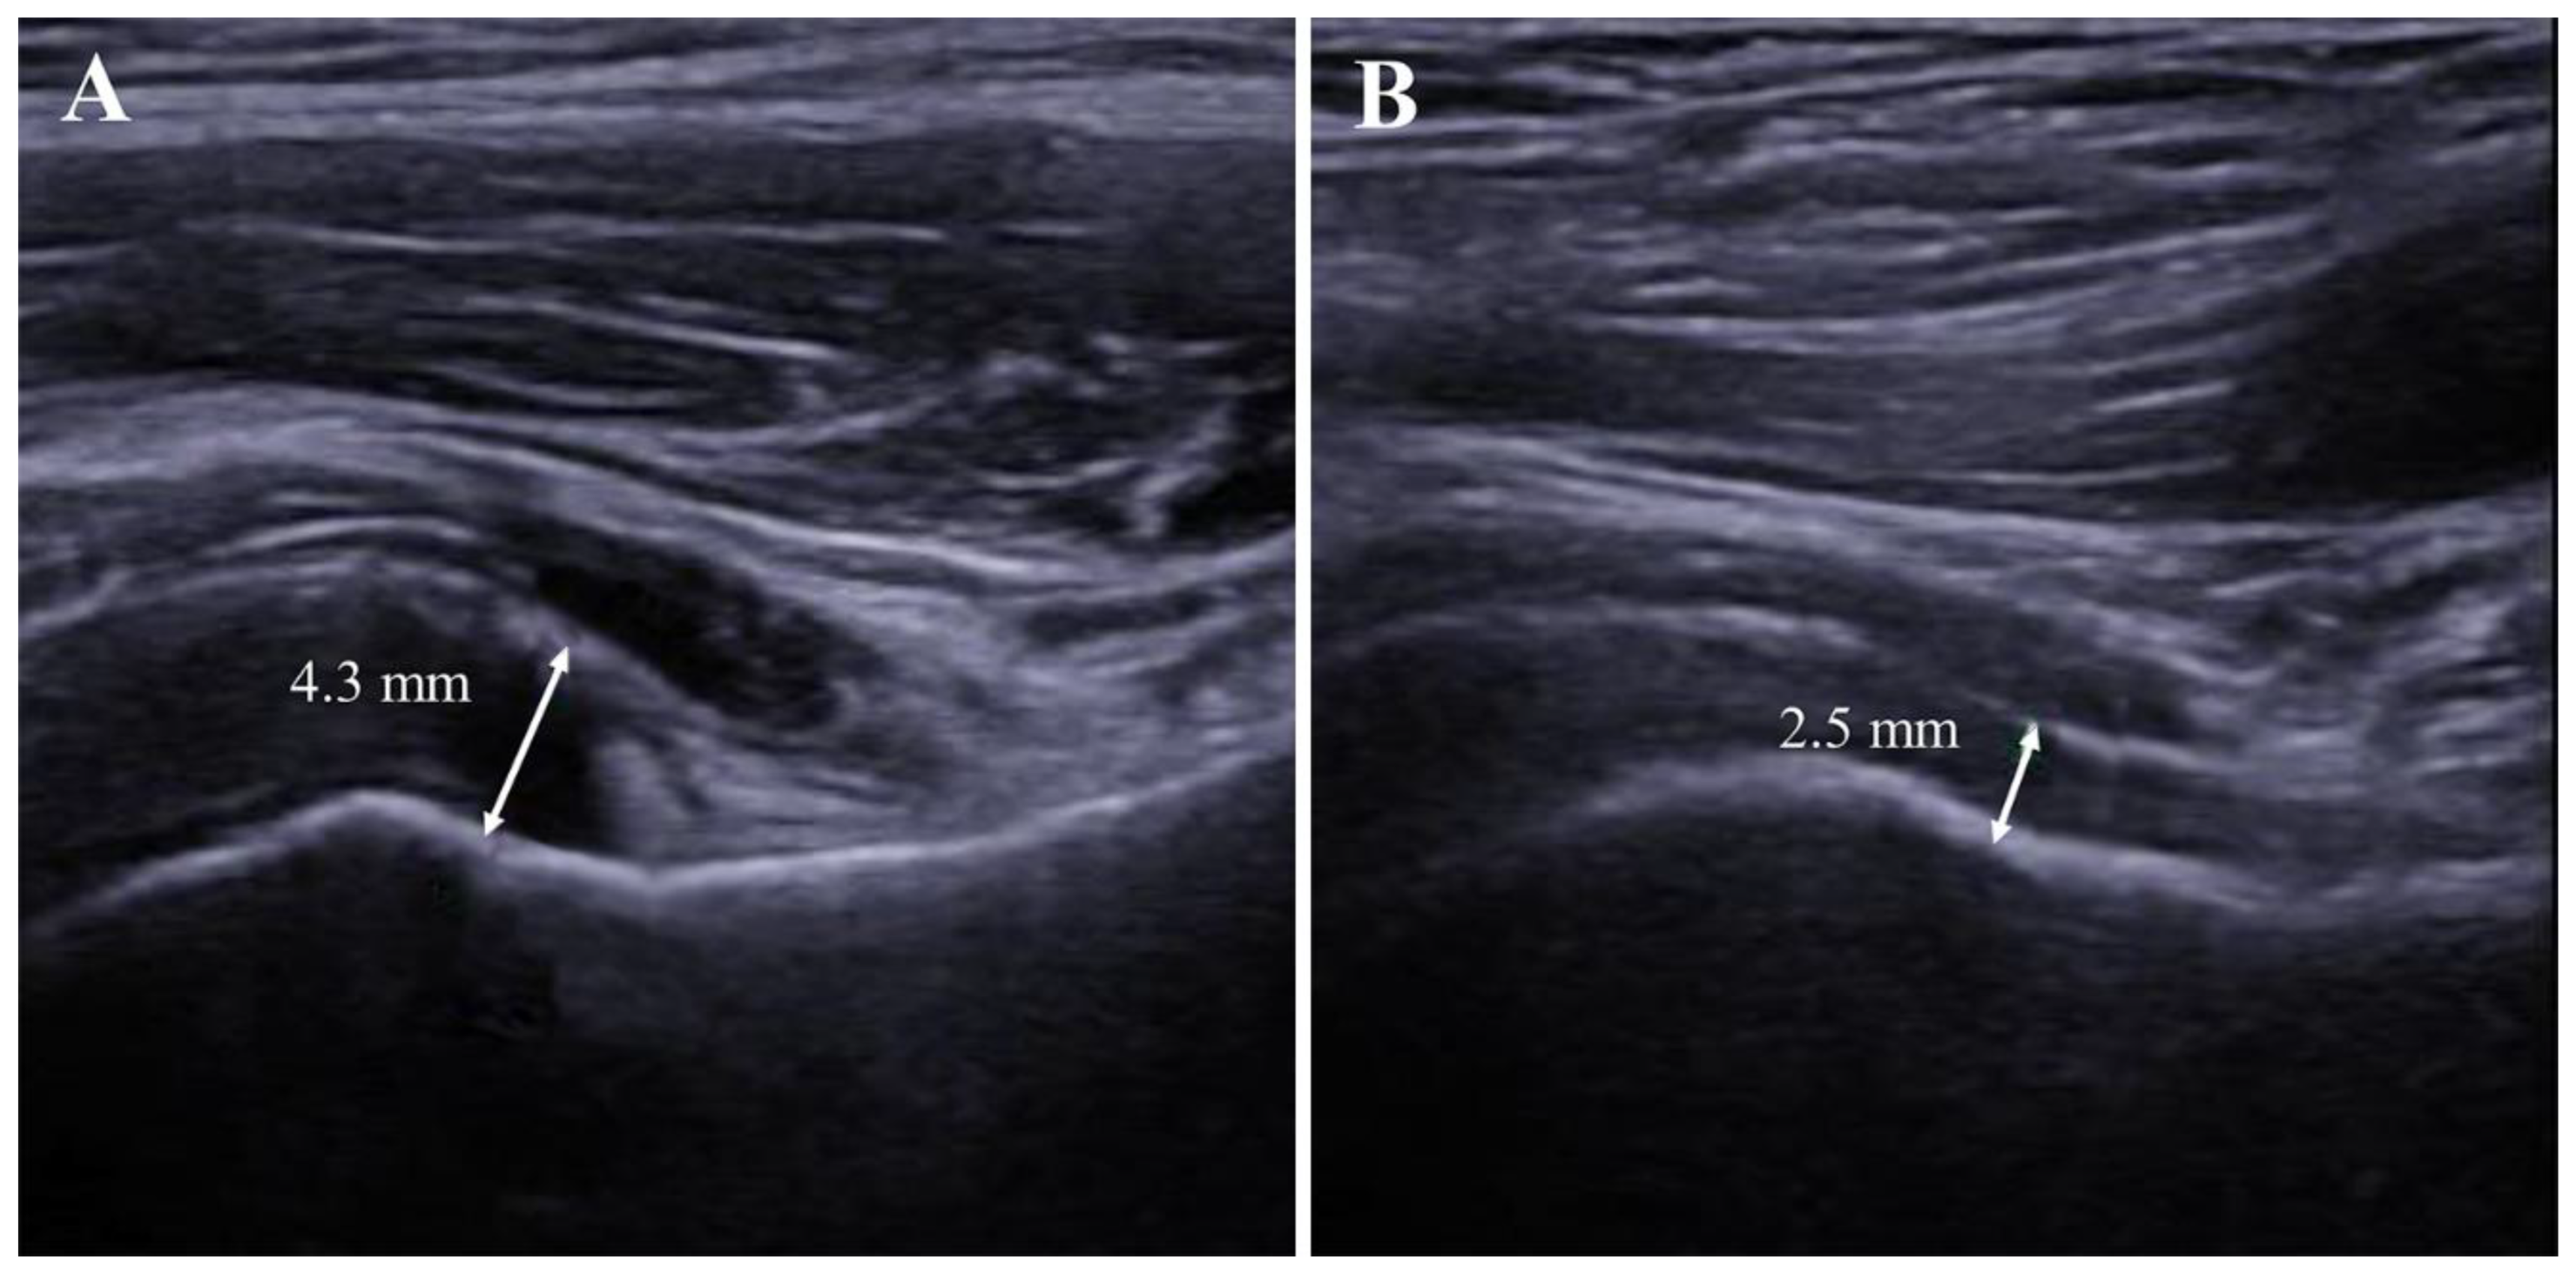

2.7. AR Thickness

| AR thickness, mm | 4.6 ± 1.6 | 2.5 ± 0.7 | <0.001 * |